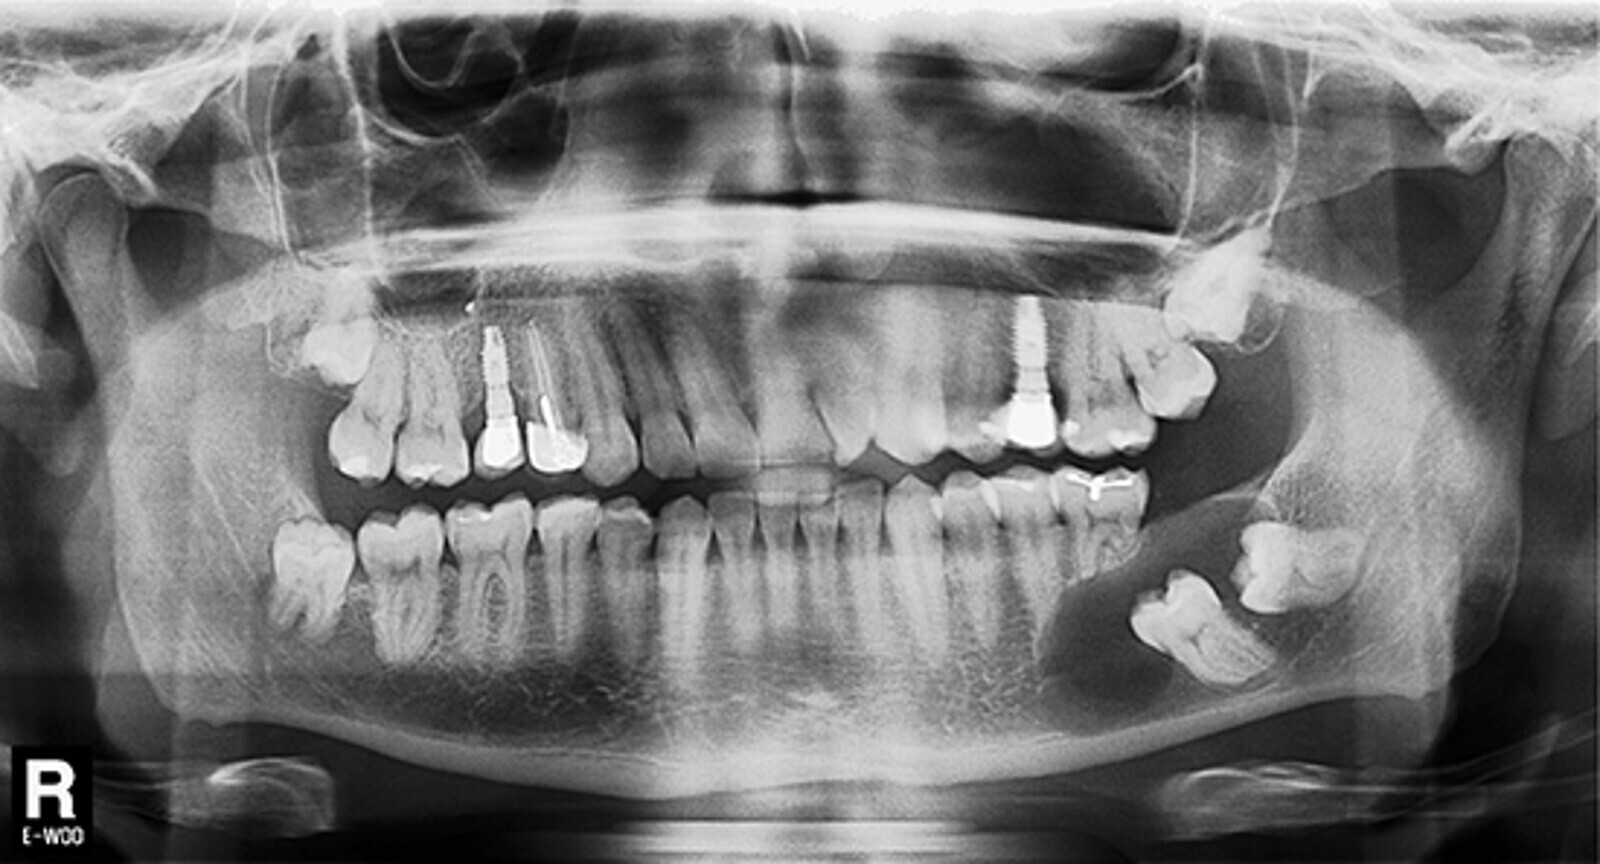

Tras realizar la evaluación radiológica bidimensional, en la ortopantomografía (Planmeca ProMax 3D Classic, Helsinki, Finland) se observó una imagen osteolítica radiotransparente que englobaba a los dientes 3.7 y 3.8 no erupcionados. Además la lesión había producido rizólisis de los dientes 3.5 y 3.6. El paciente era portador de prótesis implantosoportada a nivel 1.5 y 2.5, y había recibido tratamiento de conductos en el diente 1.4. Se observó la presencia de los cordales no erupcionados en el primer, segundo y cuarto cuadrante (Fig. 2).

Figura 2. Evaluación radiológica bidimensional. La ortopantomografía advierte la presencia de un proceso osteolítico circunscrito a las coronas de los dientes 3.6 y 3.7 no erupcionados. Nótese la reabsorción radicular de los dientes 3.5 y 3.6 debido a la extensión del proceso osteolítico en sentido antero posterior.